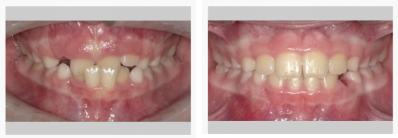

3、解除前牙、后牙反颌

5、深覆颌/深覆盖(深咬合/牙突)